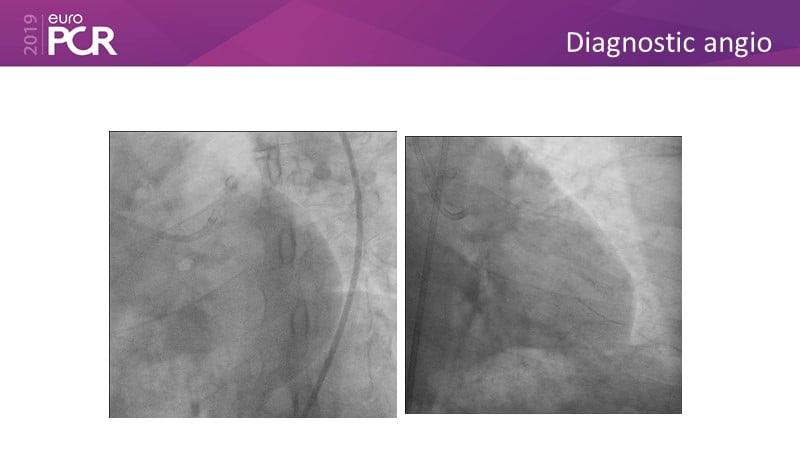

Distal left main stenosis: how to treat optimally with dedicated bifurcation stent BiOSS Lim C. Case-based session

Consult this session to learn more about the multiple technological options with dedicated bifurcation stent for complex left main bifurcation lesions, and the applicability of this stent for the different clinical presentations.